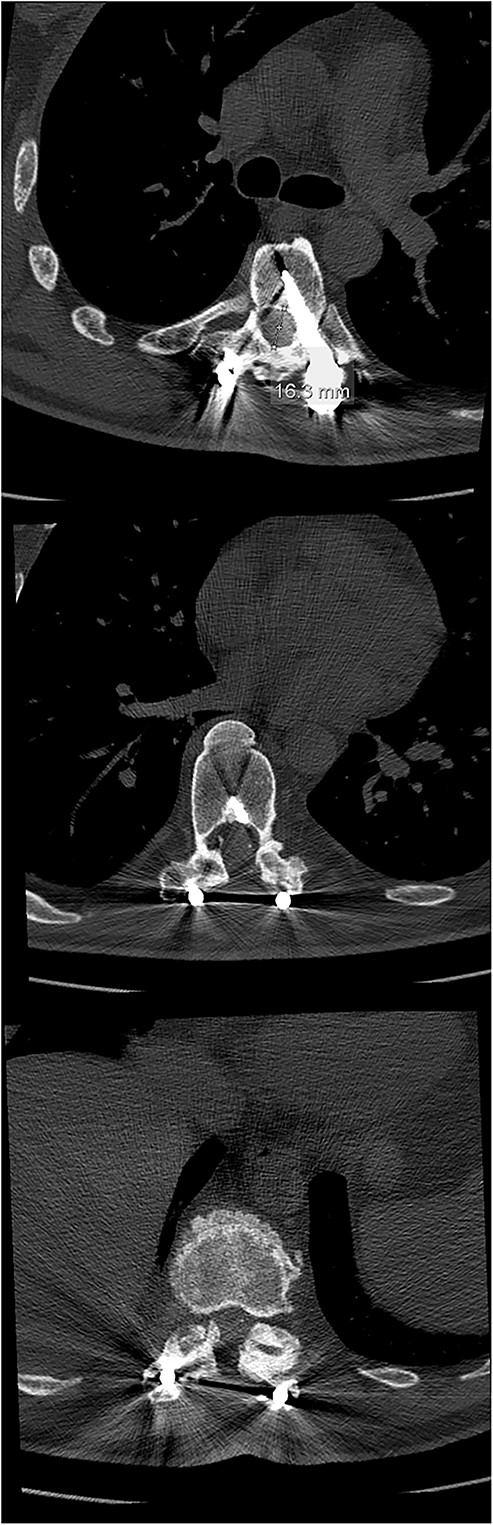

Final follow-up CT scan (axial views), showing adequate width of the spinal canal at Th6 (above), Th9 (middle) and Th11 (below).